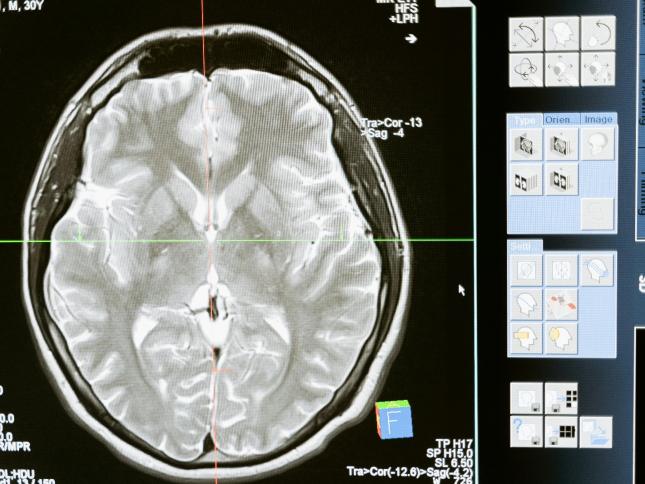

ÇEVİRİ BİLİM Yaşlandıkça zaman neden daha hızlı geçiyormuş gibi geliyor? Araştırmacılar beyin taramalarını inceledi Bilim insanları beyni genç tutan beslenme düzenini açıkladı Kötü uyumak beyni daha hızlı yaşlandırıyor Ölüme yakın deneyimlerde zaman neden yavaşlıyor?

ÇEVİRİ SAĞLIK Esrarın, kritik bir hafıza becerisine verdiği hasar tespit edildi "Bugüne kadarki en kapsamlı araştırma" Esrarın Kovid-19'la ilişkisine dair söylenenler yalanlandı Esrarın korkutan etkisi keşfedildi: Vücutta ağır metal biriktiriyor